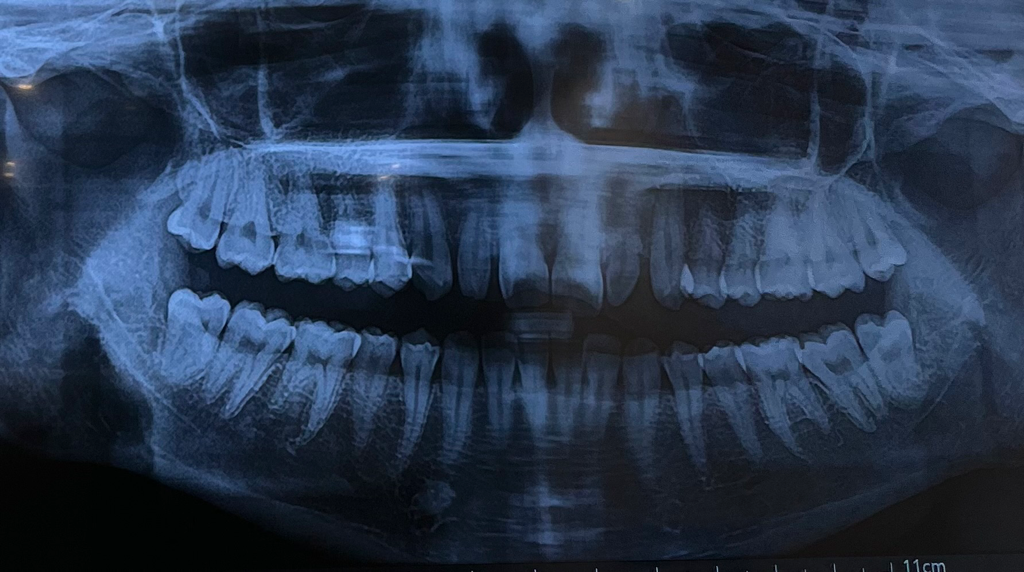

사실 파노라마 사진으로는 정확하게 판단하기는 어렵습니다. 전체적으로 보면 치아 사이에 조금씩 충치가 잇는거 같으며 정확하게 하기위해서는 작은 엑스레이 사진을 찍어봐야 알수 있습니다.

방사선사진은 파노라마가 아니고 작은 방사선사진이 필요합니다 특히 교익방사선사진으로 옆 치아들이 안겹치게 찍은 사진이 필요합니다

위 사진으로는 누구도 인접면 충치가 있다 없다 단정지을수없습니다